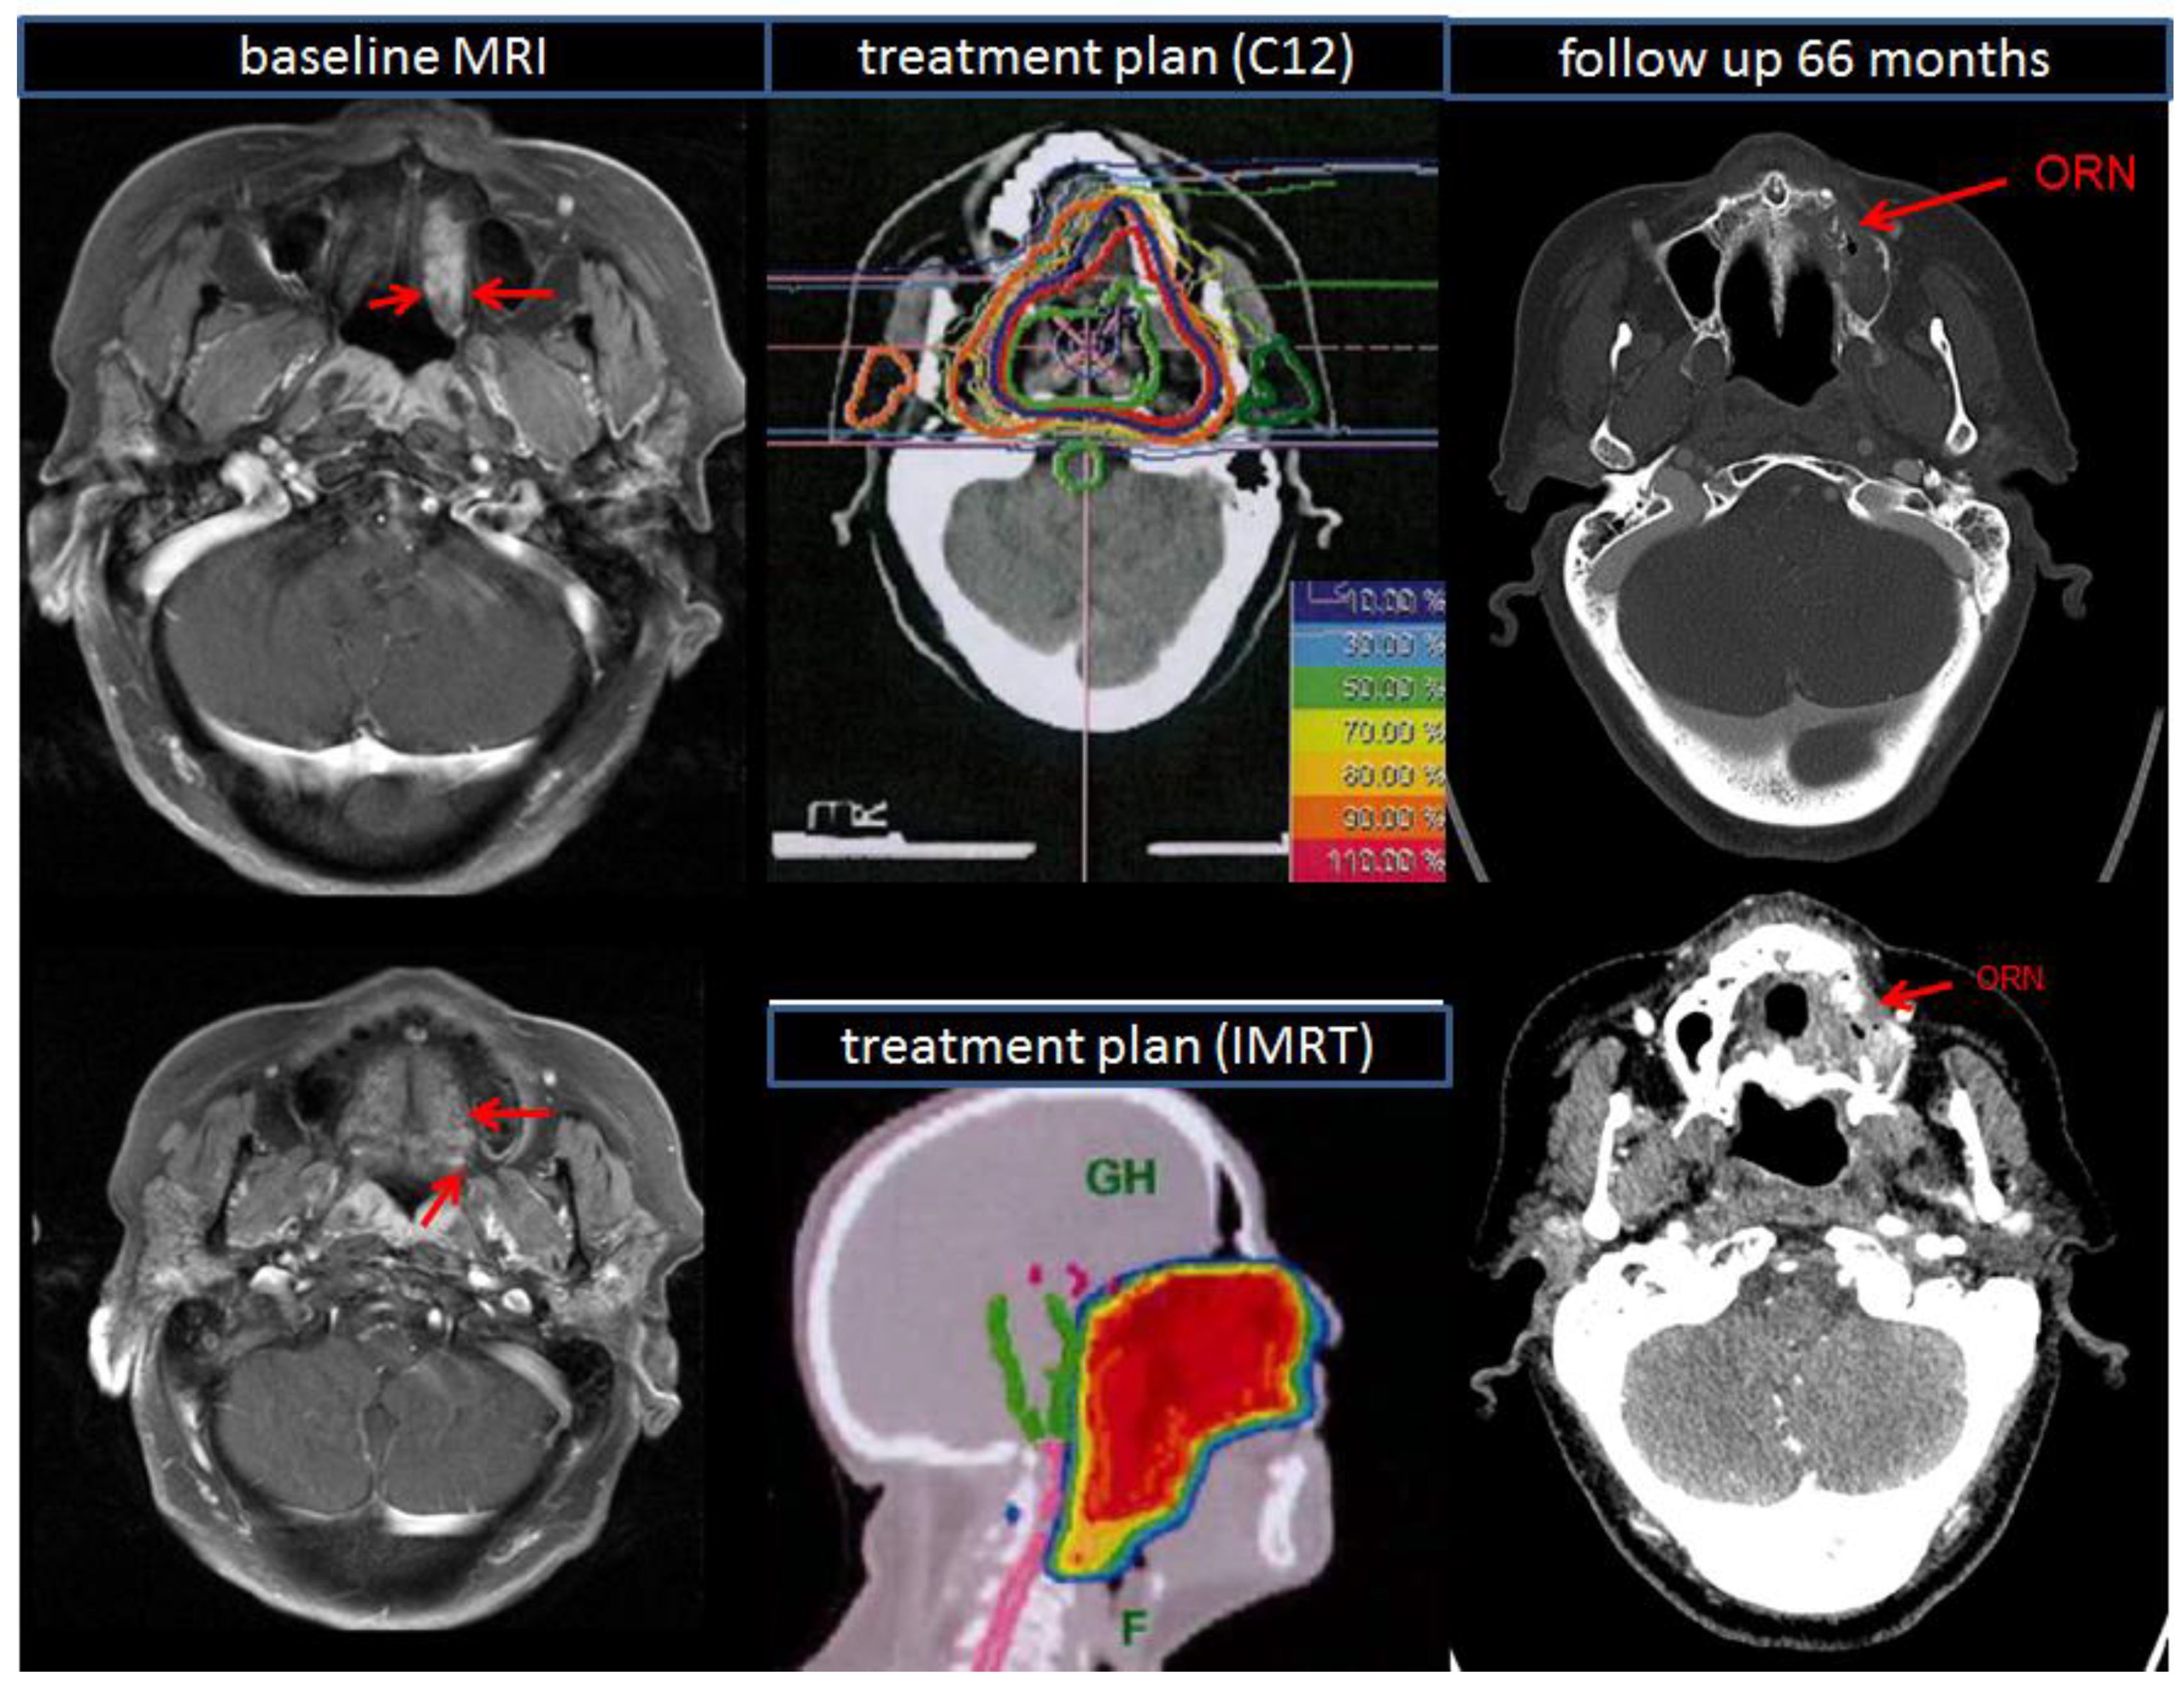

| Osteoradionecrosis | ||||||

| 3 | 2 | 3.0 | ||||